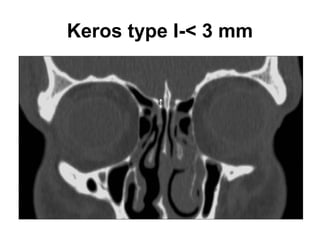

Olfactory fossa

• The depth of the olfactory fossa is determined by

the height of the lateral lamella of the cribriform

plate, which is part of the ethmoid bone. In 1962,

Keros had classified the depth of the olfactory

fossa into three types, that is,

• Keros type I: <3 mm,

• type II: 4-7 mm , and

• type III: 8-16 mm.-Kero type III is most

vulnerable to iatrogenic injury.

Keros type I-< 3 mm